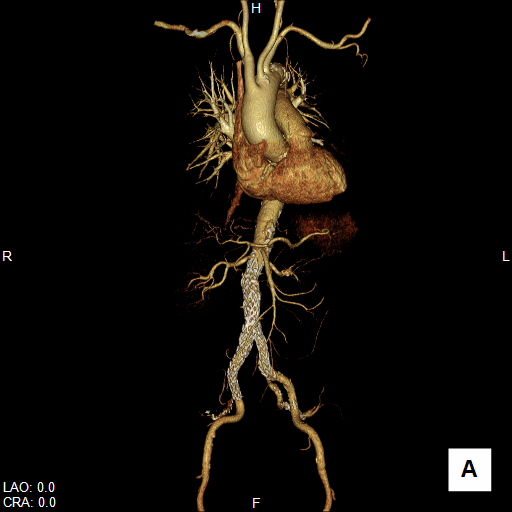

大動脈疾患の診断では、①瘤/解離の範囲と位置、②血流評価、③主要分枝・周囲臓器との関係、④並存疾患の評価、⑤ステントグラフト治療の可能性評価などが必要です。

CTは、体軸方向に分解能の高いボリュームデータを短時間かつ広範囲に得ることができるので、体軸方向に広いスキャンが必要な大動脈疾患の検査に適しています。大動脈病変と分枝動脈の関係だけでなく、分枝動脈自身の評価も可能ですから、手術前シミュレーションや、インフォームドコンセントの参照画像にも有用です。

腹部大動脈瘤へのステントグラフト内挿術評価CT